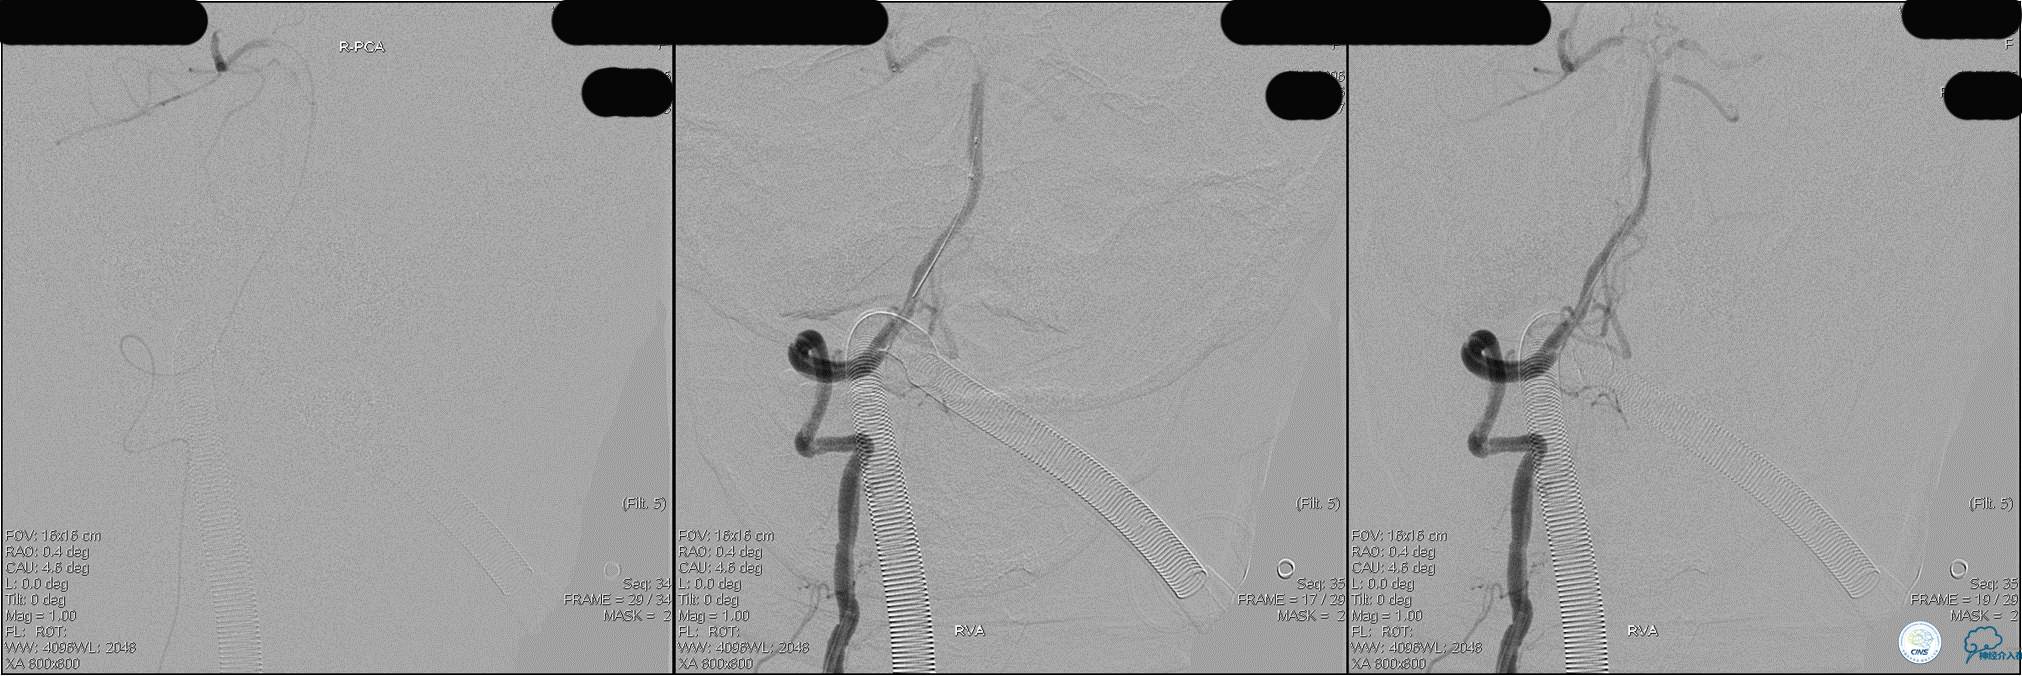

》DSA资料(经桡动脉,5F导引导管)

》DSA资料(右侧椎动脉)

》DSA资料(前2次取栓,未取出,soli 4-20)

》DSA资料(第3次取栓)